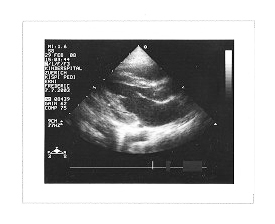

Dies ist ein Bild von Frédéric’s Herz beim Echokardiogramm drei Tage nach seiner Herzschrittmacheroperation.